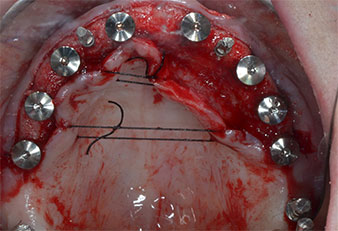

Fig. 1: Pre-operative view of the maxillary ridge, with implant positions marked with the aid of a surgical plastic template. Due to the low ridge super short posterior implants are planned.

Implant positions

Fig. 2: After mid-crestal incision and preparation of mucoperiosteal flaps the implant positions are transferred to the bone.